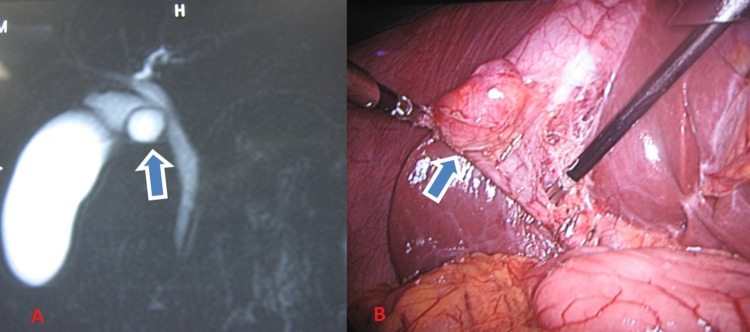

Another case was a 23-year-old female with complaints of only pain in the right upper abdomen for four months, with no symptoms of jaundice and fever. Clinical examination revealed no significant findings. Laboratory investigations revealed no abnormality. On initial evaluation with ultrasonography of the abdomen showed a hypoechoic lesion in the region of GB neck with no gall stones. On further evaluation with MRCP was found to have a cystic lesion at the GB neck with a normal CBD. Preoperatively she was diagnosed as type 2 CDC. Intraoperatively, it was an isolated cyst of the cystic duct (type 6A) of size 2 × 2 cm2 with a narrow opening at its juncture with CBD, and CBD was normal (Figure 3). Laparoscopic simple cholecystectomy was done. Post-operative histopathology report showed cyst wall lined by biliary epithelium and peribiliary glands with acute or chronic inflammatory infiltrate without any evidence of malignancy. The post-operative period was uneventful. She is doing well after five years of follow-up.